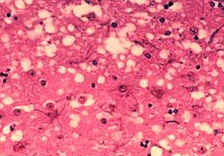

이 프리온은 현재 알려진바에 의하면 포유류에 몇 종의 질환을 일으키며 이 질환으로 가장 흔하게 알려진것이 광우병입니다. 이 광우병은 소해면상뇌증이라고 불리우며 이 질환은안타깝게도 사람에게도 발생하기도 합니다. 사람에게 발생할경우에 코로이츠펠트-야코프병이라고 불리웁니다. 혹은 씨제이디[CJD]라고 칭하기도 합니다.